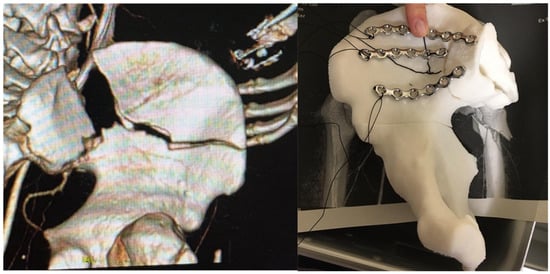

Anatomical model for pre-modeling synthesis plates for surgical treatment of acetabular fractures (traumatological surgery)

The treatment of pelvic fractures involves a complicated approach for the osseous pelvis, which contains viscera and large vessels that make handling difficult. These fractures require complex bone reconstruction using osteosynthesis plates, which must be perfectly adjusted to the patient’s anatomy. Current surgical methods entail a great loss of time during the operation, sometimes with a difficult and/or dangerous approach, which limits the final retouching of the plates. This final adjustment of the plates is performed at the surgeon’s discretion and requires great expertise [41]. The trial-and-error method necessary to obtain an appropriate molding presents the disadvantage of excessive operating time, which is not convenient for the patient. The combination of reverse engineering with AM can provide a solution to this problem. Thus, the plates can be molded before the operation based on a previously printed biomodel obtained directly from a scan of the patient, reducing the operating time and costs and providing benefits for the patient, such as less exposure and lower infection risk [41,42] (Figure 5).

The planning and personalization of the treatment result in a reduction in complications, as well as reductions in clinical variability and surgeon dependence. The surgical technique based on 3D models provides safety and confidence to the clinician and better clinical results, such as shorter operation time, less intraoperative blood loss and less intraoperative fluoroscopy. The 3D model is used, in addition to planning the surgery, to improve the coordination of the surgical team, to teach residents and to explain the process to the patient, which, as already mentioned in the previous cases, gives him/her peace of mind and confidence.

Figure 5. Anatomical model for pre-modeling synthesis plates for surgical treatment of acetabular fractures (traumatological surgery). Left: CT image, volumetric render of bone fracture. Right: Anatomical model for preformed osteosynthesis plates manufactured by SLA technology.